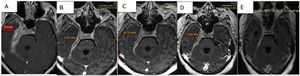

Discusión de las imágenesEn los estudios sucesivos de resonancia magnética se evidencia tejido patológico que engrosa las meninges con un espesor de 19,5mm, y que muestra señal isointensa en T1, hipointensa en T2 y tiñe con el contraste con moderada restricción a la difusión del agua.

Compromete la base de cráneo en topografía parasagital derecha, con extensión hacia el conducto carotídeo, foramen yugular, agujero rasgado posterior, peñasco y tienda del cerebelo homolateral. Invade. Además. el conducto auditivo interno, el seno cavernoso y el vértice de la órbita derecha, con compromiso paquimeníngeo a nivel de la fosa temporal profunda rodeando circunferencialmente los pares craneales III, V, VI, segmento cisternal e intracavernoso, VII y VIII a nivel del conducto auditivo interno.

Se observa progresión de la paquimeningitis con compromiso de la región anterior del quiasma óptico, el cual se observa engrosado con refuerzo poscontraste. Reemplaza a la vena yugular interna derecha en su foramen, no evidenciándose opacificación del segmento proximal de la misma. Defecto de relleno parcial del seno sigmoideo homolateral.

Comparativamente se observa respuesta parcial al tratamiento instaurado con relación al estudio de base con espesor paquimeníngeo de 19,5mm al inicio; en los controles presenta disminución de 10,5mm (53% del tamaño inicial) a la semana del pulso de corticoides; a 8,7mm (44% del inicial) con corticoides más rituximab; y en el último control, luego de 3 meses del inicio del tratamiento, con corticoterapia de mantenimiento 10mg/día de prednisona y metotrexato presenta 7,8mm (40% del tamaño inicial) (figs. 3A-D).

Secuencias en T1 de la RMN sucesivas en la evolución de la paciente. Desde (A) lesión basal con engrosamiento de aproximadamente 2cm, hasta (D) estado posterior al tratamiento con esteroides y rituximab que evidencia la mejoría franca del engrosamiento y el edema. E) Cortes tardíos que muestran zonas de fibrosis.

En el último control se observa disminución del engrosamiento paquimeníngeo descrito en los estudios anteriores, a nivel del quiasma, del conducto auditivo interno, del seno cavernoso, y espesor de fosa temporal; y al realizarse cortes tardíos a los 30min se identifica mayor realce del tejido paquimeníngeo en relación a componente fibrótico (fig. 3E).